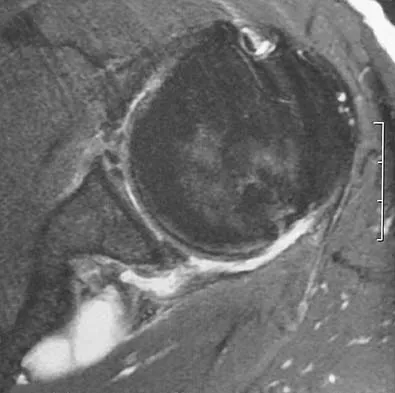

A 25-year-old tennis player has shoulder pain and weakness to external rotation. MRI scans are shown in Figures 16a and 16b. What is the most likely cause of his weakness?

Explanation